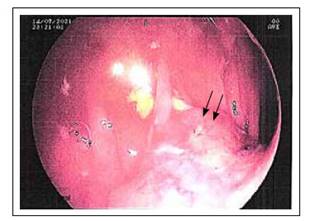

Mujer de 68 años refirió un tiempo de enfermedad de 2 meses caracterizado por anemia, dolor abdominal y hemotoquezia, motivo por el cual se le indicó estudio colonoscópico, en el que se identificó, a nivel de colon ascendente, lesión neoproliferativa, ulcerada y con bordes elevados friables, no estenosante (Figura 1), que al estudio anatomopatológico en otra institución fue reportado como adenocarcinoma infiltrante NOS de bajo grado. Con ello, la paciente fue programada para una colectomía radical derecha laparoscópica. Macroscópicamene, a nivel de colon ascendente, se corroboró la presencia de tumor pardo gris de bordes elevados, ulcerado de 4,0x3,5x1,2 cm. El estudio patológico informó que la tumoración correspondía a carcinoma adenoescamoso con infiltración hasta la subserosa, sin presencia de embolia linfovascular, ni compromiso ganglionar. La evolución de la paciente fue favorable, por lo que, al quinto día post cirugía, fue dada de alta (Figura 2).

Figura 1 A nivel de la mucosa próxima a ciego, se identifica lesión proliferativa, ulcerada, de bordes elevados y friables, no estenosante.